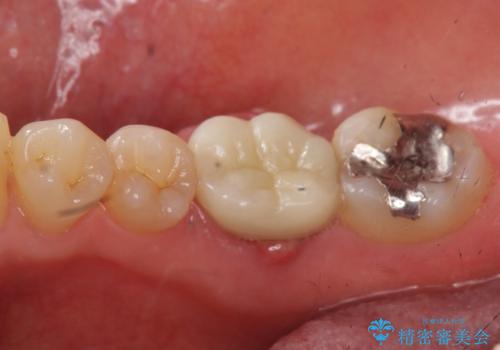

また、根の詰め物が根尖孔外(根の先の外の骨の部分)に盛大に漏れ出しており、歯周ポケットと根尖病巣が交通しているような状態でした。

被せ物を外したところ、歯が大変薄くなって割れており、残念ながら残すことはできないと説明しました。

初めての根の治療には見えないくらい、かなり歯が削ってあり、薄くなっていて割れても仕方ない状態でした。前の状態を見ていないので何とも言い難いですが、他の歯に比べこの歯だけ極端に状態が悪かったです。